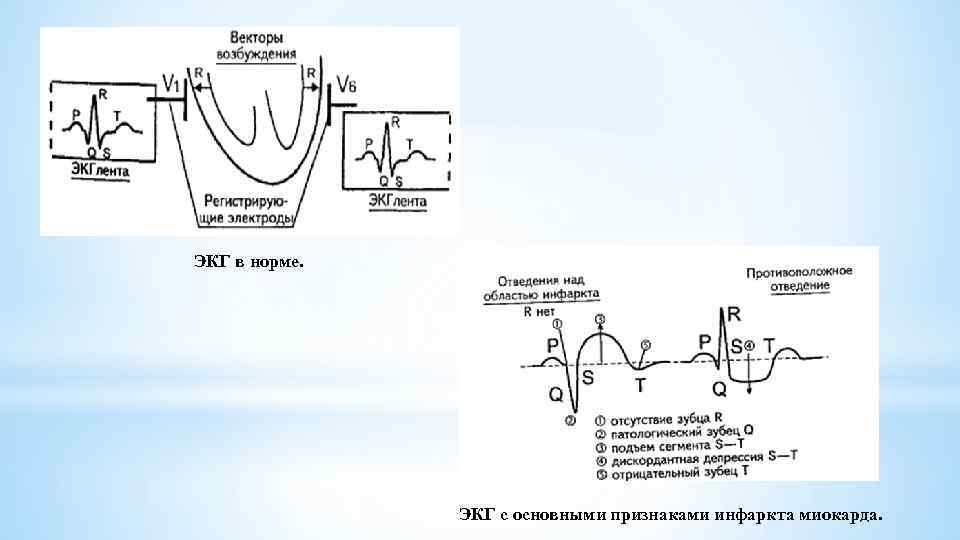

ЭКГ в норме. ЭКГ с основными признаками инфаркта миокарда.

ЭКГ в норме. ЭКГ с основными признаками инфаркта миокарда.